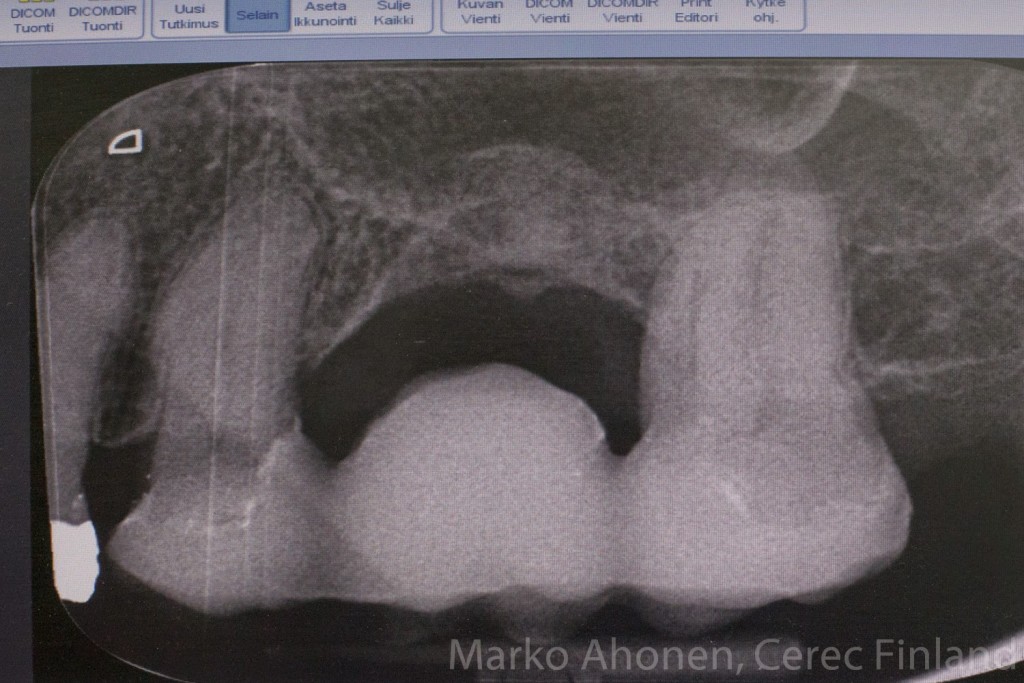

Potilaan juurihoidettu takaposkihammas d.16 oli jouduttu laajan tulehduksen johdosta noin viikko sitten. Hammas oli alunperin suositeltu jo poistettavaksi kaksi vuotta sitten. Potilas ei tottunut eikä halunnut olla ilman hammasta joten lähdin suunnittelemaan hampaan korvaavaa hoitoa. Usein implantti on yksittäisen hampaan korvaamisessa paras vaihtoehto. Tässä tapauksessa implantti ei tullut kyseeseen luun vähyyden johdosta (ktso rtg-kuva lopussa) joka johtui pitkään jatkuneesta tulehduksesta. Lisänä potilas ei halunnut odottaa eikä lähteä laajoihin luusiirteisiin. Viereisten hampaiden laajat amalgaamipaikat puolsivat myös sillan tekemistä. Sillassa viereiset hampaat hiotaan tukipisteiksi sillalle jolloin vanhoat paikat saadaan korvattua keraamisilla kruunuilla.

Röntgenkuvassa nähdään täysdigitaalisesti tehdyn sillan erinomainen istuvuus (ohut sementtisauma, spacer 80um step bur 12):

IMG_3268